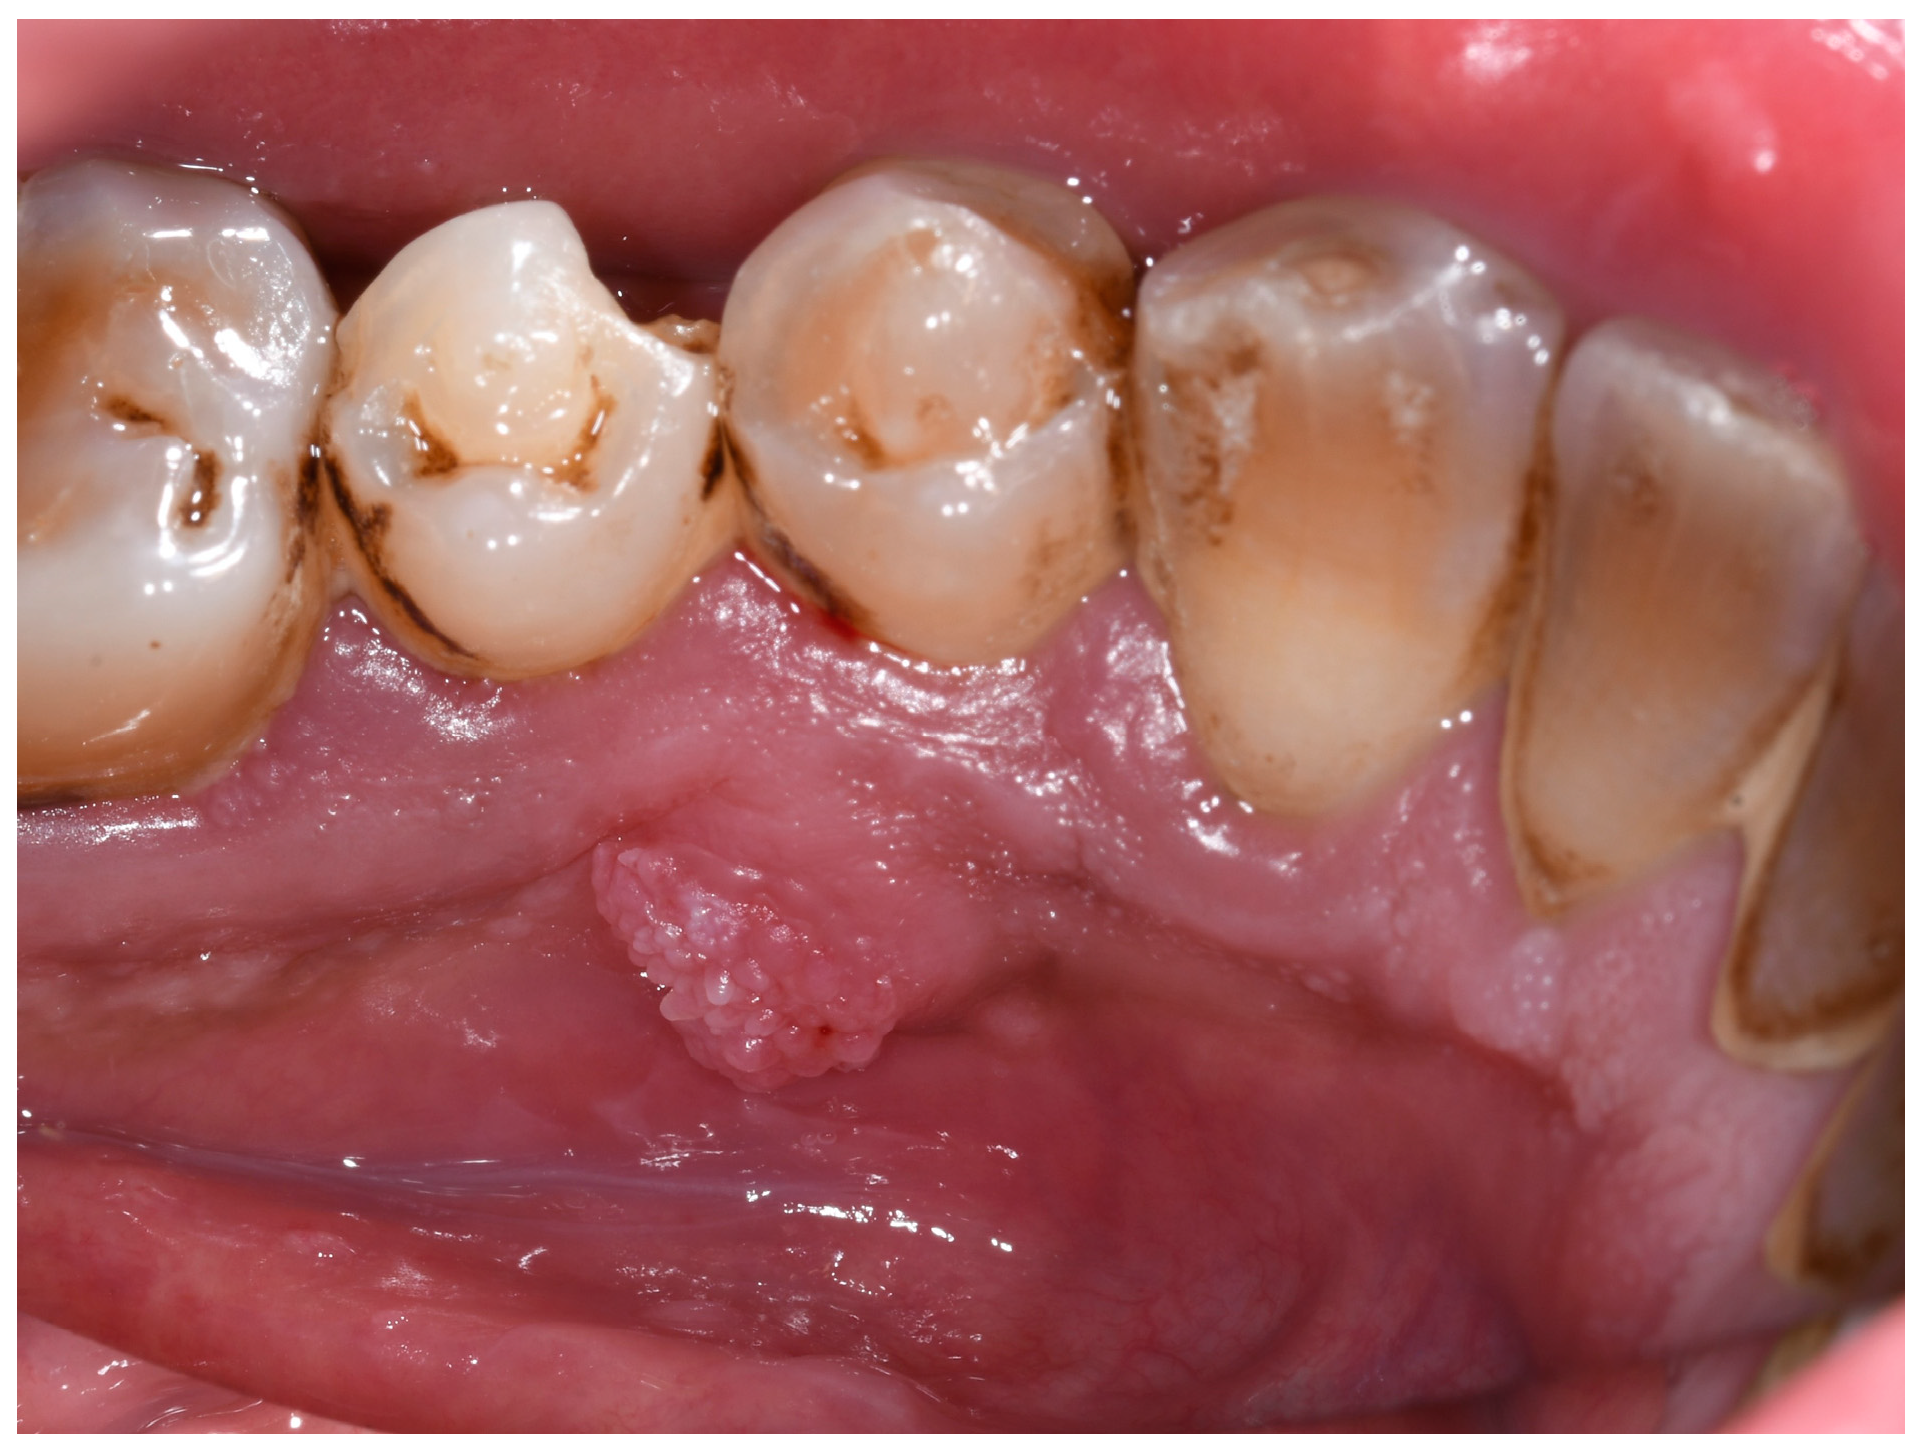

Case Presentation